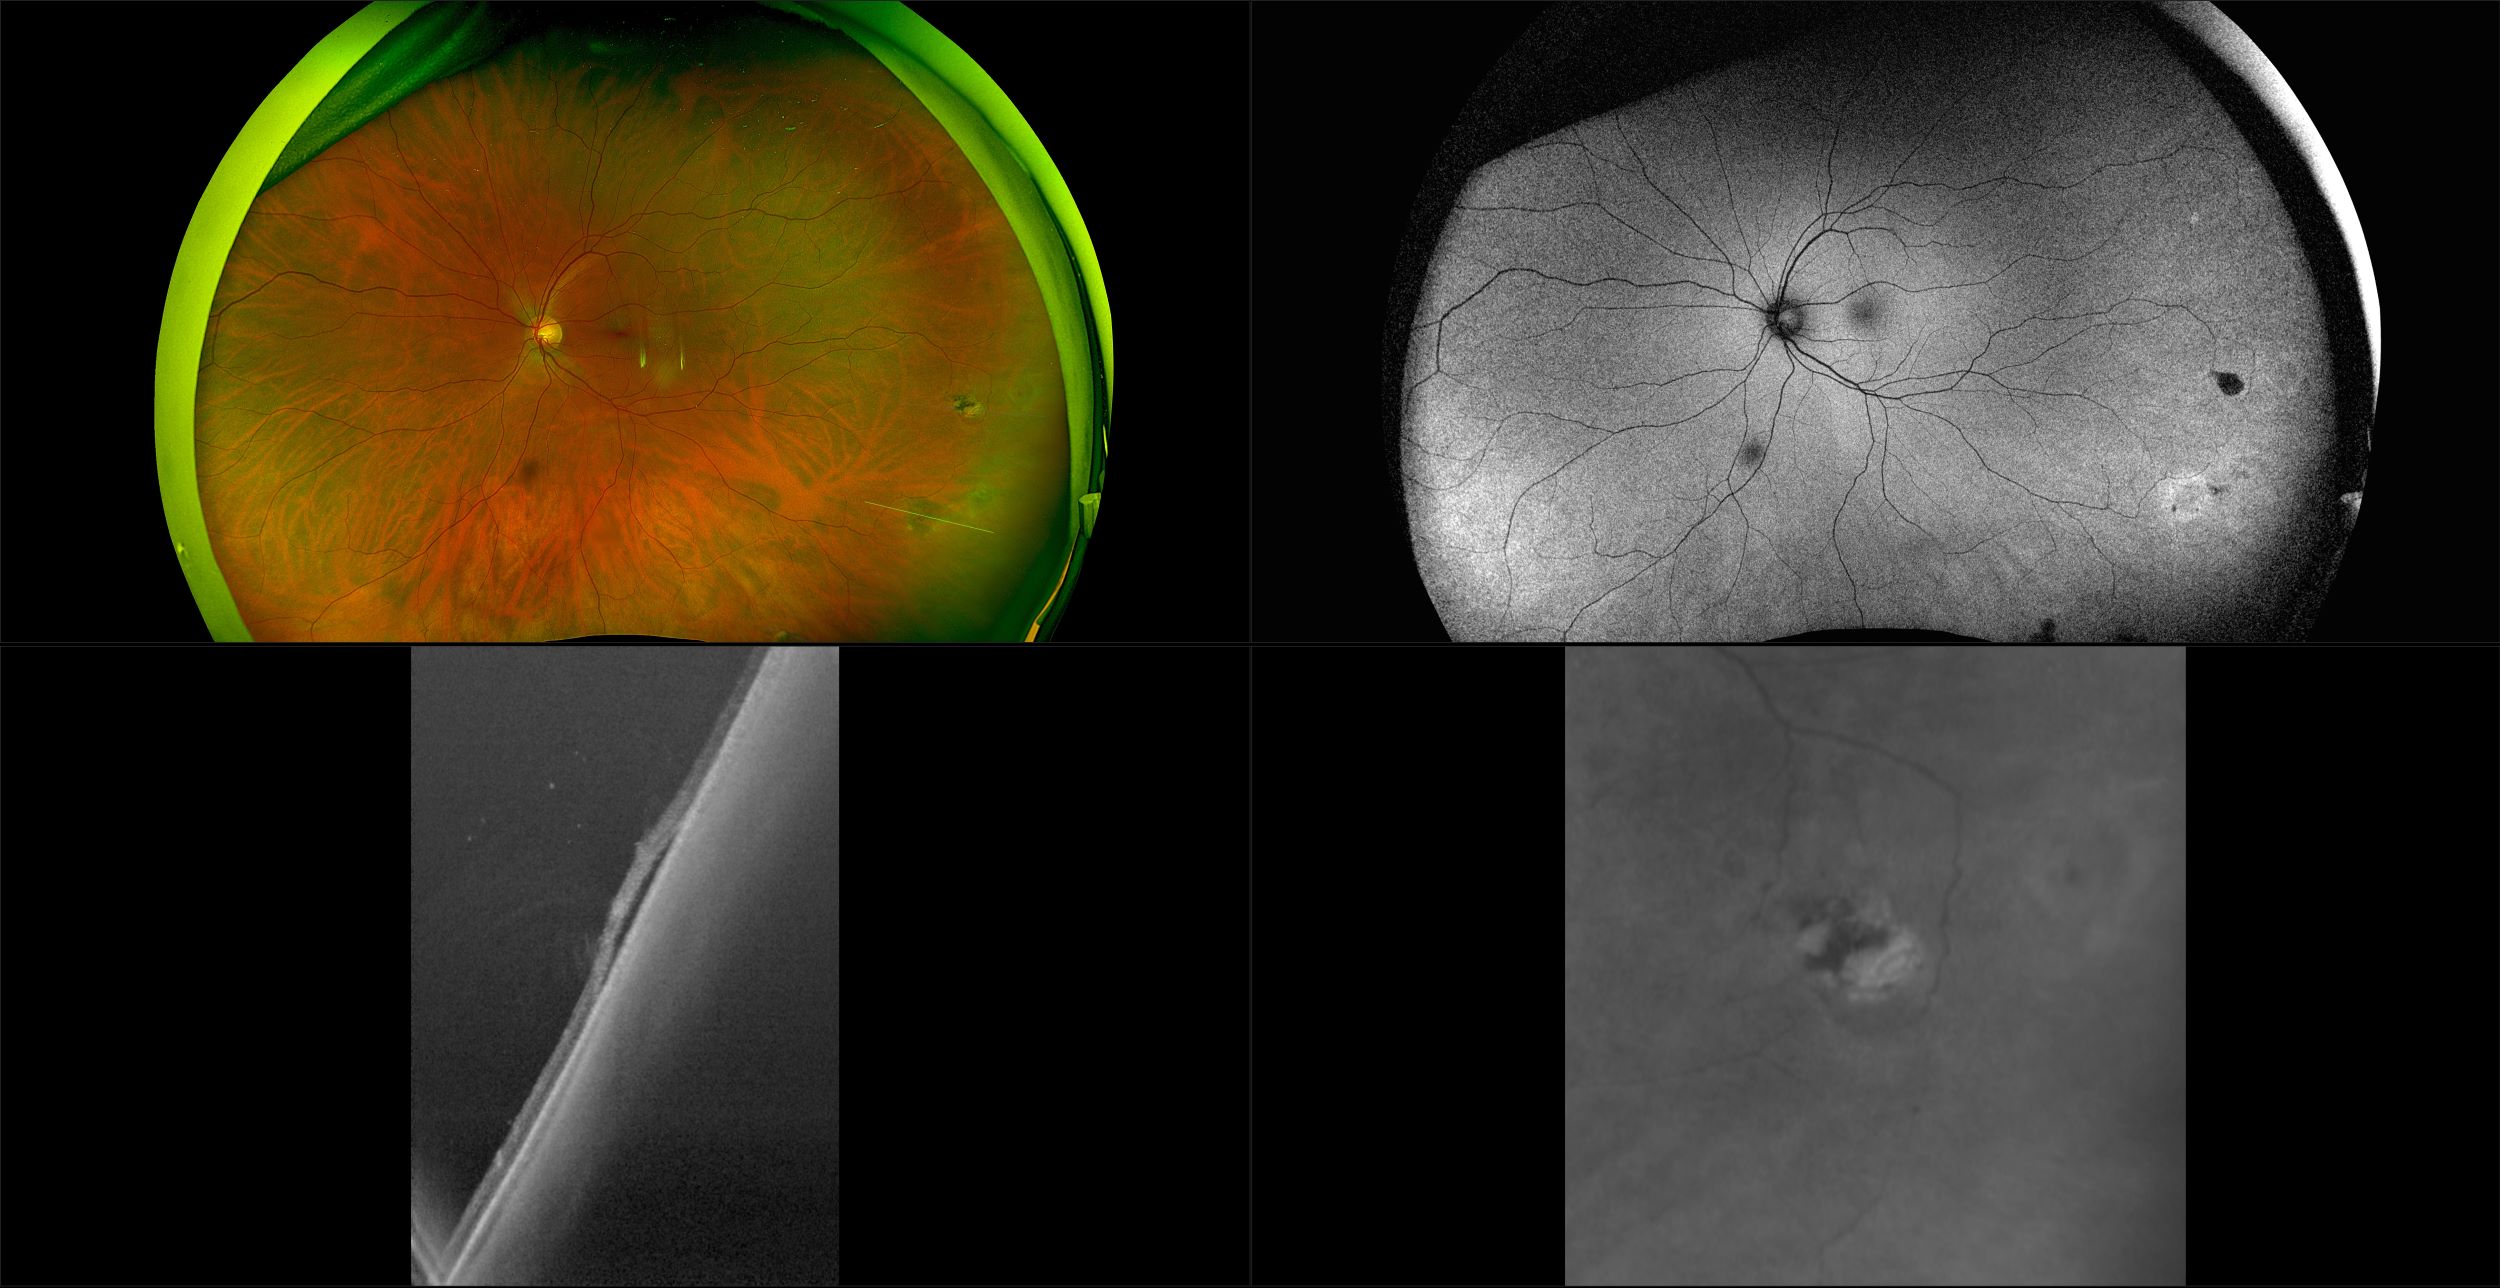

Monaco - Pigment Epithelial Detachment, RG, OCT